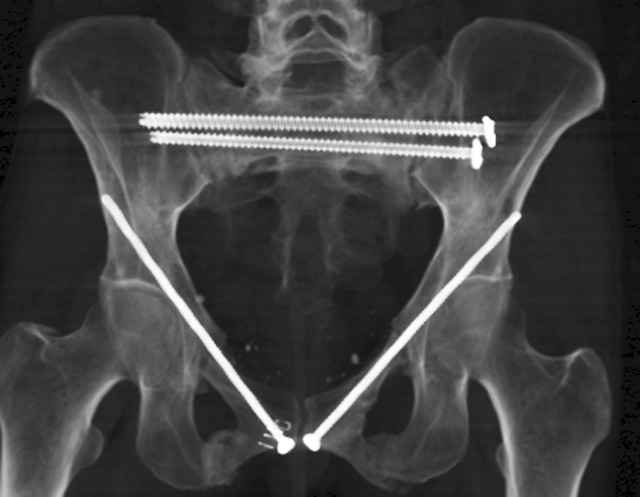

Percutaneous Fixation

(B) Ramus-Retrograde

2 TransIliac-TransSacral

Upper Segment